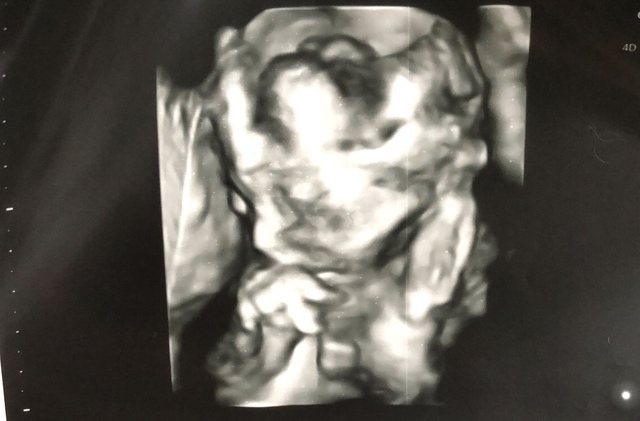

21週5日(21w5d・男の子)|慶ちゃんママ さん(26歳)

エコー写真撮影時のエピソード:

赤ちゃんのお顔が見たくて、毎回の検診をとても楽しみにしていたのに、中々お顔を見せてくれなかった。

私も旦那も人見知りで内気の性格だが、この写真一枚で赤ちゃんにも性格が遺伝していることがわかる。 なぜならば、 恥ずかしいのか赤ちゃんが顔の前で両手をグーにして隠していて、顔を見せてくれないからだ。

毎回の検診で、今日はお顔見せてねと喋りかけて臨んでいたが、結局生まれてくるまで顔を見せてくれることはなかった。